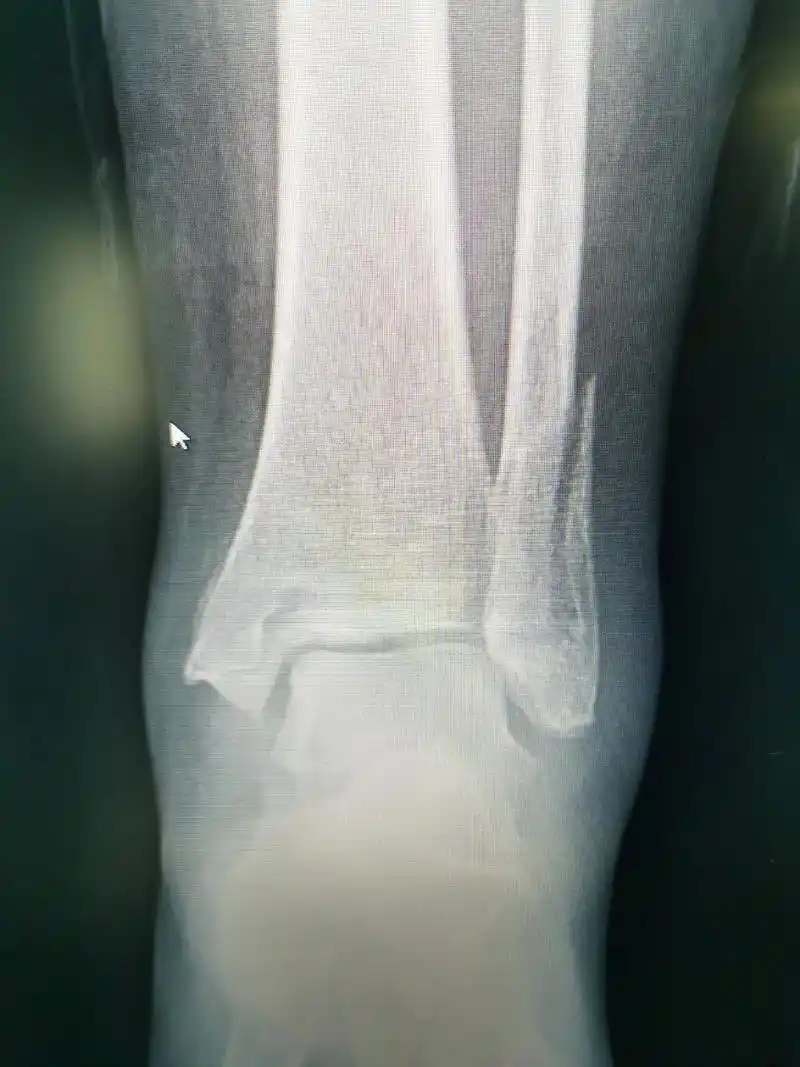

本例患者扭伤所致,踝关节 - 抖音